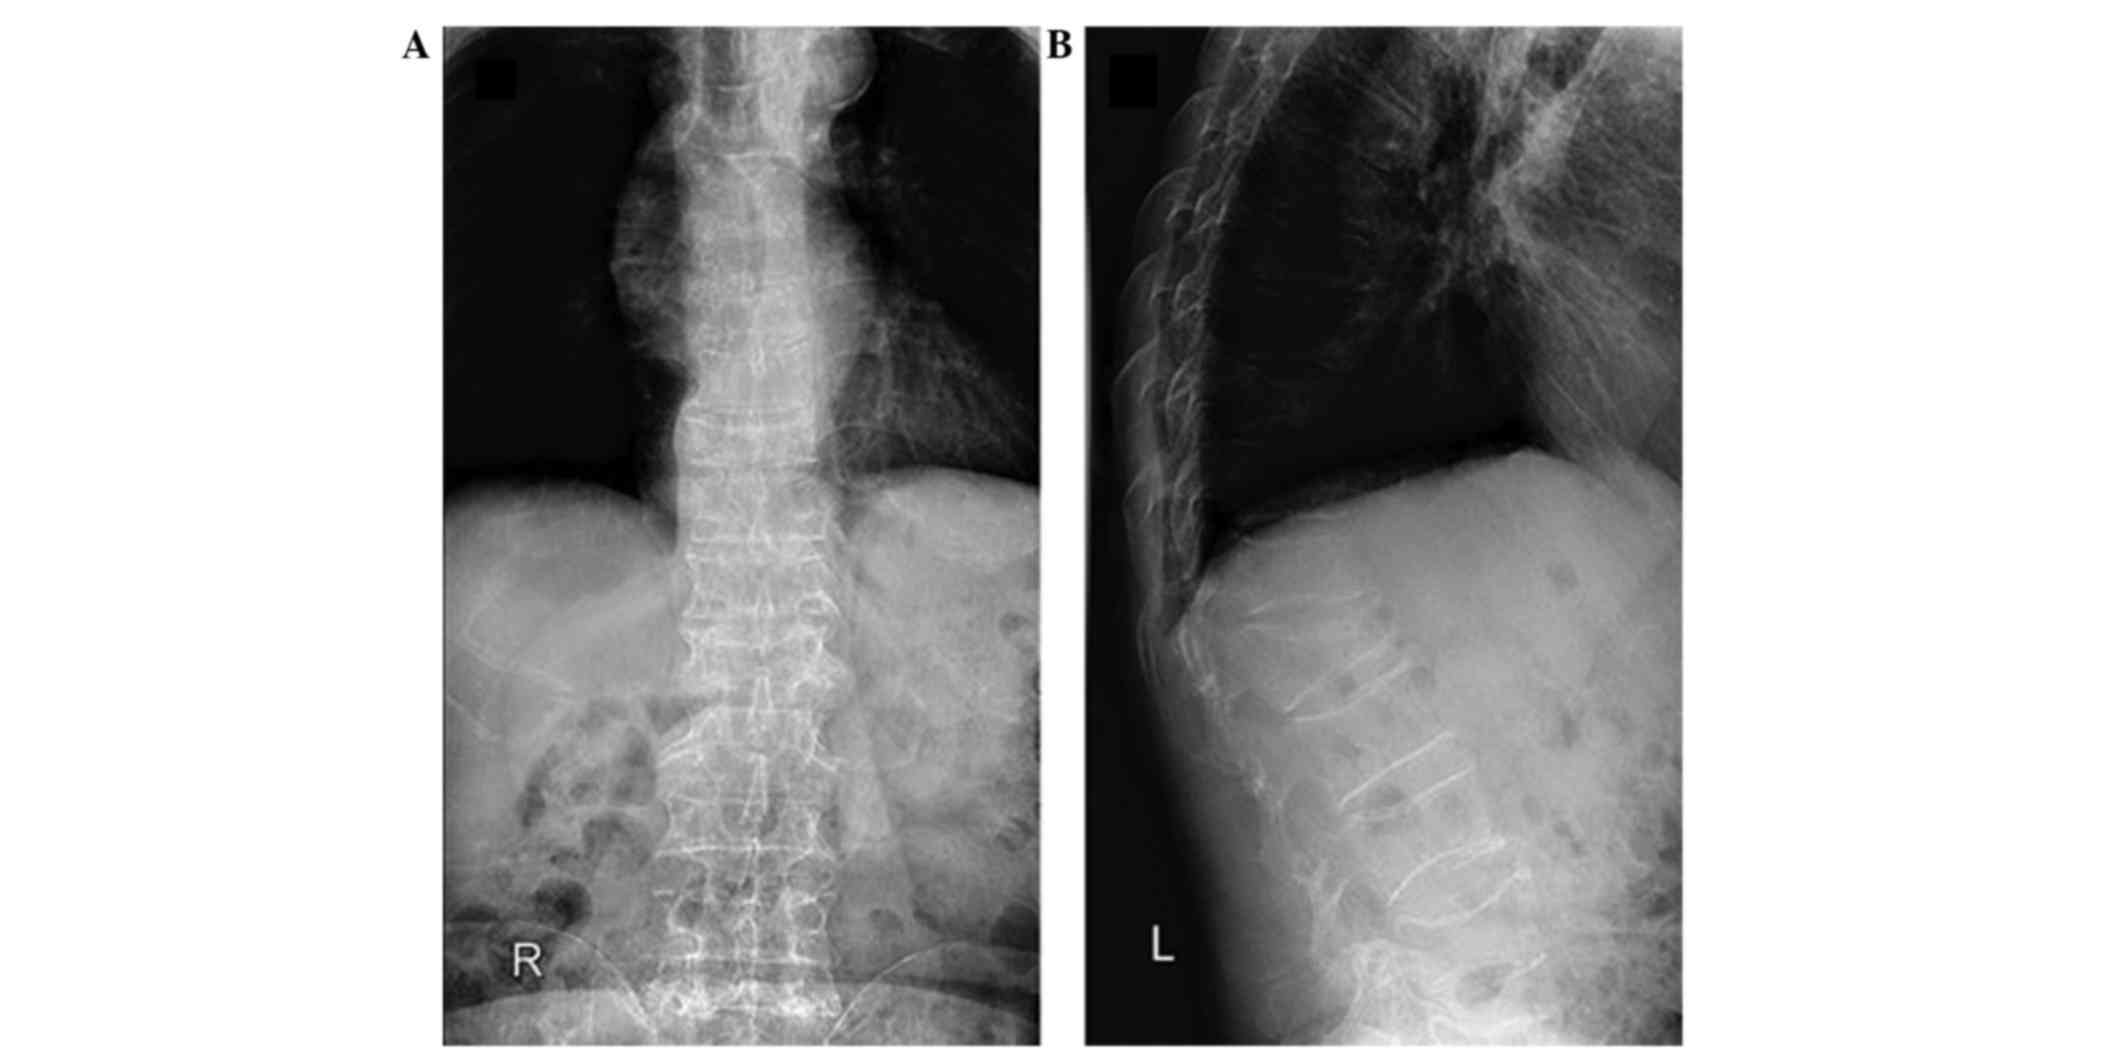

Case report

Figure 4.

Postoperative (A) anteriorposterior and (B) oblique radiographs, revealing satisfying fracture reduction and cement distribution.